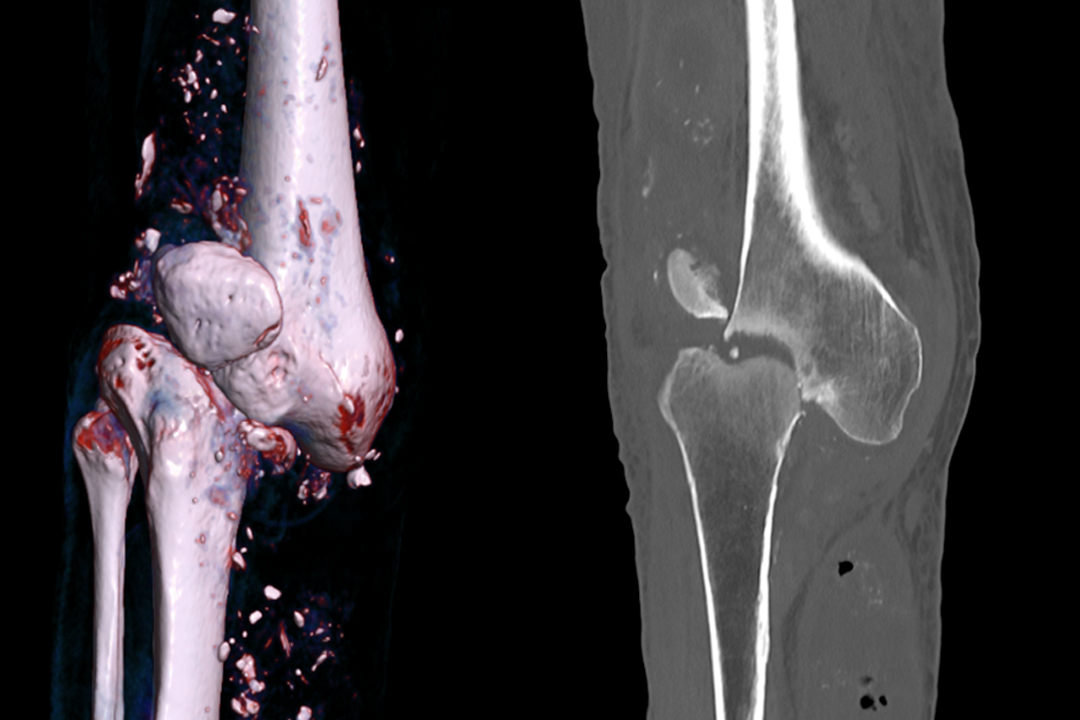

Se complementaron los estudios de imágenes con una tomografía computarizada y reconstrucción 3D (Fig. 1- Ver la imagen en alta definición) que mostró una fractura conminuta desplazada, del cóndilo femoral lateral, asociado a subluxación femorotibial, pérdida de la ubicación y morfología de la patela, irregularidades y esclerosis de los platillos tibiales y derrame articular heterogéneo con zonas de calcificación.

Por las características clínicas e imagenológicas, se consideró como diagnóstico una RC Eichenholtz-I (tabla 1) secundaria a una NA, por su enfermedad metabólica de base. Se realizaron intervenciones consistentes en inmovilización con férula de yeso, un plan de rehabilitación enfocado en mejorar la condición general, prevenir complicaciones y tratamiento del dolor con medicamentos gabapentinoides con ajuste de dosis, por las características mixtas de dolor y enfermedad renal de base.